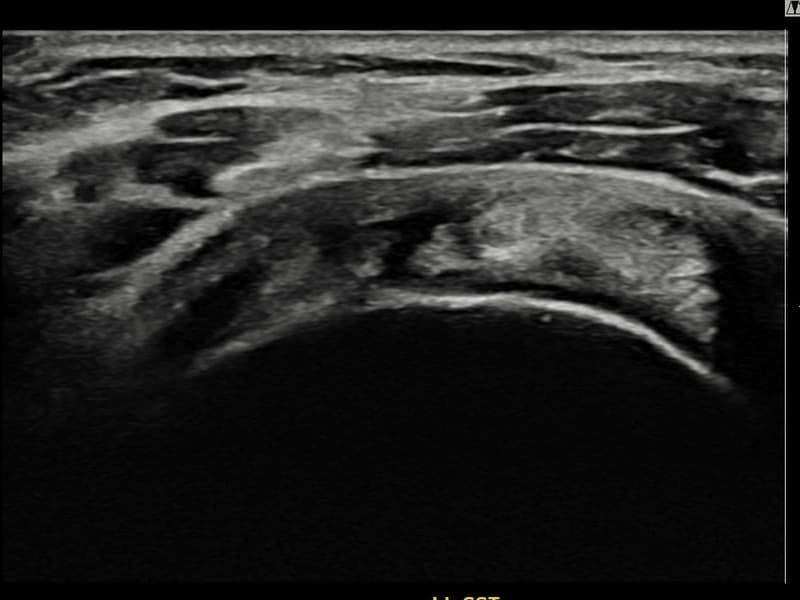

施術前

術前超音波にて左 棘上筋腱 滑液包面側部分断裂・左肩棘上筋腱のエコー不連続と腱欠損(14mm × 7mm (腱厚の約65%欠損))を確認。術後超音波では断裂部位が再生組織で充填され、腱の連続性回復とエコーパターンの正常化が確認されました。